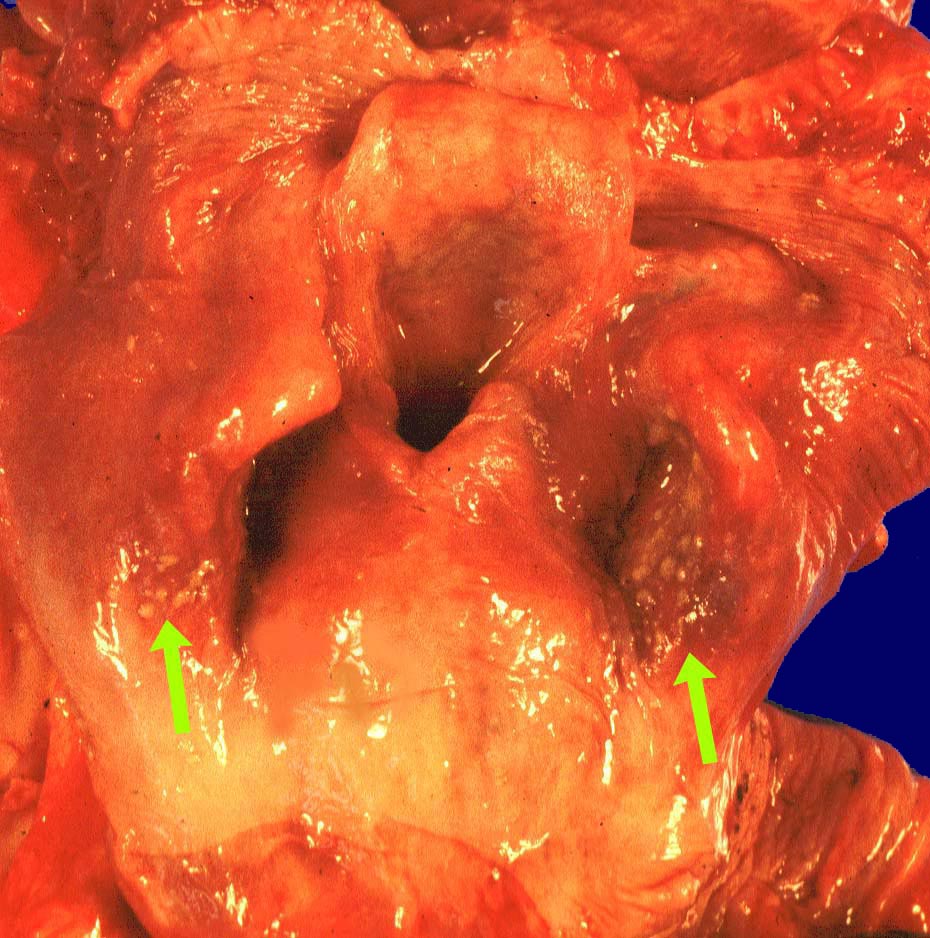

PathoPic ID 1424 - Soorösophagitis

Soorösophagitis

Entzündung infektiös

Oropharynx

Kopf & Hals, Sinnesorgane

Oropharynxschleimhaut mit runden, leicht erhabenen

Auflagerungen.

Makroskopie